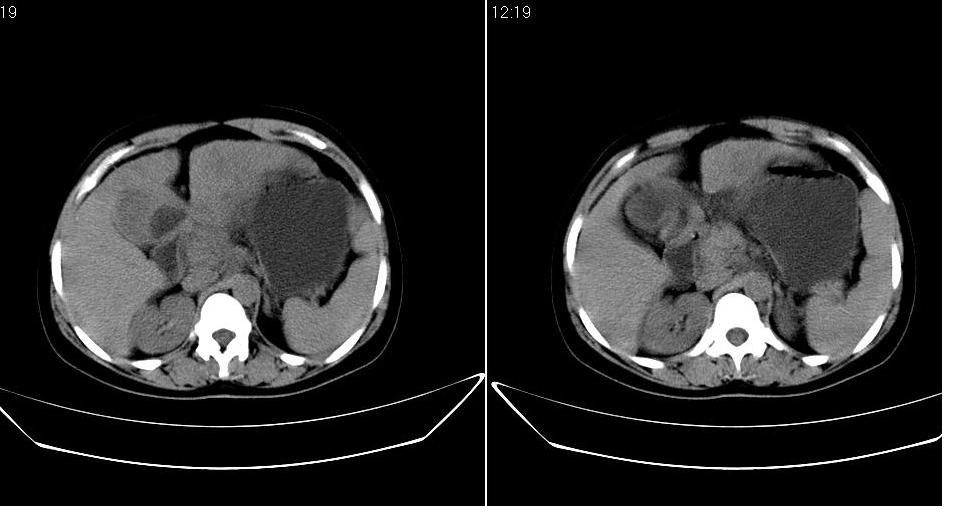

女 36岁,腹痛月余,b超提示肝左叶占位,腹水。

肝脏左叶明显增大,各叶比例失调,左叶实质内不均匀低密度影,似乎有肝内胆管的扩张,没有增强实在不好判断,不知患者肝功能是否正常,我觉得象胆管细胞癌。

肝脏左叶明显增大,各叶比例失调,左叶实质内不均匀低密度影,增强!

1)考虑肝左叶肝癌;建议行进一步检查。2)肝硬化,脾稍大。3)双侧少量胸腔积液。

肝脏左叶明显增大,且左叶实质内不均匀低密度影。考虑左叶占位??建议增强后再讨论。